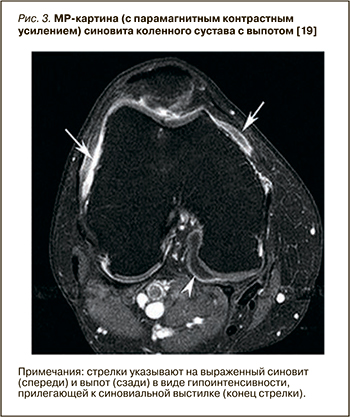

Синовит при артроскопии наблюдается примерно у 50% пациентов с болевым ОА коленных суставов, а при проведении МР-исследовании выявляется еще чаще [17]. Сравнение данных МРТ, гистологических и артроскопических характеристик синовиальной оболочки у лиц с симптоматическим ОА коленного сустава [18] показывает высокую корреляцию между степенью утолщения синовиальной оболочки на МРТ и макроскопической оценкой синовита при артроскопии (r=0,58), а также инфильтрацией воспалительных клеток под поверхностные слои синовии (r=0,46). На рисунке 3 представлено изображение МРТ с парамагнитным контрастным усилением, где определяется выраженный синовит и выпот в виде гипоинтенсивности МР сигнала.

120-1.jpg (107 KB)Проведено множество исследований с использованием МРТ, показывающих связь наличия и выраженности синовита и болевого синдрома при ОА коленного сустава [20, 21]. Для выявления синовита предпочтительно МР-исследование с применением контрастного усиления, поскольку контрастное вещество улучшает внешний вид синовиальной оболочки без акцента на других тканях. Так, МРТ с гадолиниевым усилением показало, что синовит более распространен у пациентов с болью в коленном суставе, причем риск возникновения умеренной и сильной боли в суставе при наличии синовита достоверно возрастает. Даже у людей без очевидных рентгенографических признаков ОА, а только с небольшой потерей хряща на МРТ, указывающей на раннюю стадию заболевания, при наличии обширного синовита заметно увеличивался риск появления боли [22]. В открытом исследовании O’Neill T.W. et al. 120 пациентам было проведено сканирование с контрастным усилением до и после внутрисуставной инъекции глюкокортикостероидов [23]. Через 2 нед у пациентов с уменьшением болевого синдрома было отмечено уменьшение выраженности синовита. Кроме того, у пациентов с рецидивом боли в течение 6 мес увеличился объем синовиальной ткани.